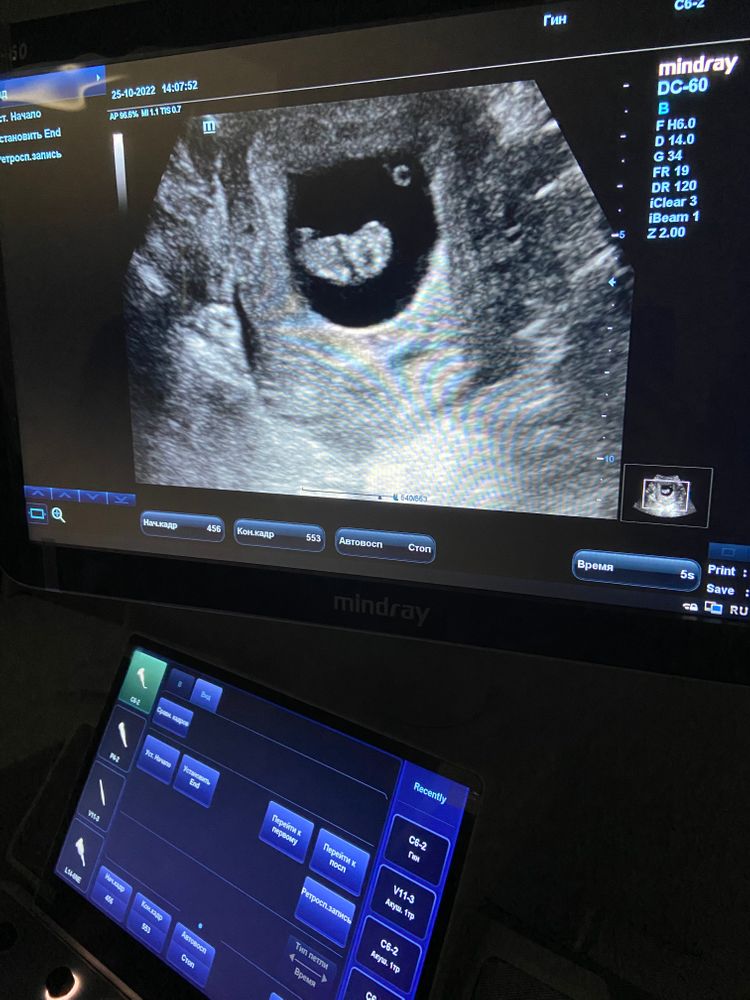

Сходила я на узи , чтобы уменьшить свою тревожность)) переболела , плюс был большой стресс , переживала все ли хорошо с малышом.

Слава богу все в порядке😍показали мне фасолинку)))) сердечко бьется , ручки , ножки шевелятся ))) потом пришла домой и ещё допплером поймала сердечко ❤️❤️❤️